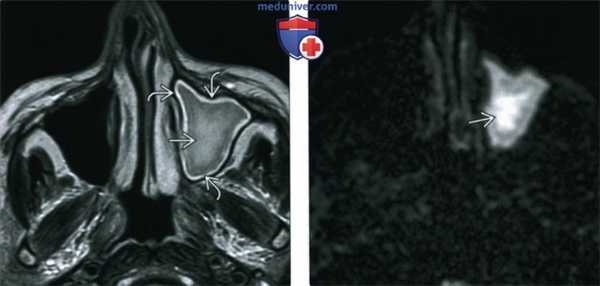

(Слева) При аксиальной МРТ Т2 ВИ у пациента с ХРС определяется снижение пневматизации левой верхнечелюстной пазухи. Содержимое в центре пазухи отчасти гипоинтенсивно из-за малого количества воды и большого количества белка. По периферии определяется воспаленная гиперинтенсивная слизистая оболочка.

(Справа) При аксиальной MPT DWI у этого же пациента определяется диффузное повышение интенсивности сигнала в левой верхнечелюстной пазухе, заполненной содержимым. Определяется рестрикция диффузии, наиболее выраженная в центре.

4. МРТ при хроническом риносинусите:

• Т1ВИ:

о Утолщенная слизистая оболочка изоинтенсивна мягким тканям

о Интенсивность сигнала в содержимом зависит от количества воды и белка:

- Чем больше белка, тем выше интенсивность сигнала (Т1)

• Т2ВИ:

о Слизистая оболочка обычно гиперинтенсивна

о Содержимое пазухи может быть гиперинтенсивным (↑ воды) или гипоинтенсивным (↓ воды, «сухое» содержимое)

о Утолщение стенок пазухи очевидно на MPT (Т2 ВИ)

• Т1ВИ С+:

о Типичное контрастное усиление слизистой оболочки

о Контрастирование не требуется в неосложненных случаях